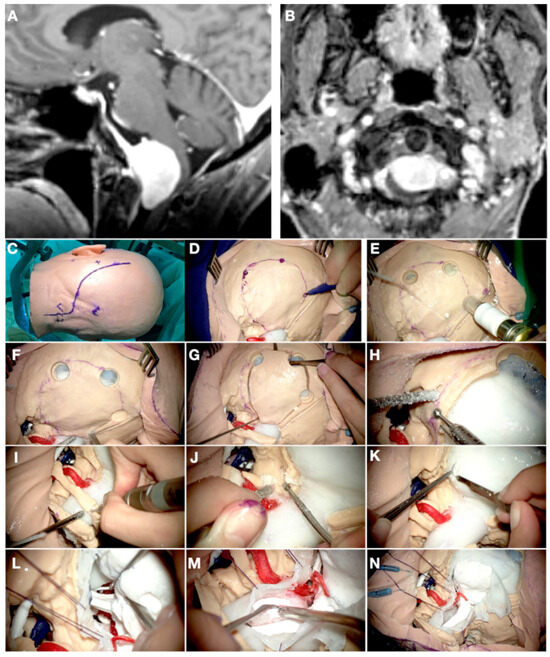

3.4. Case 4: Foramen Magnum Meningioma